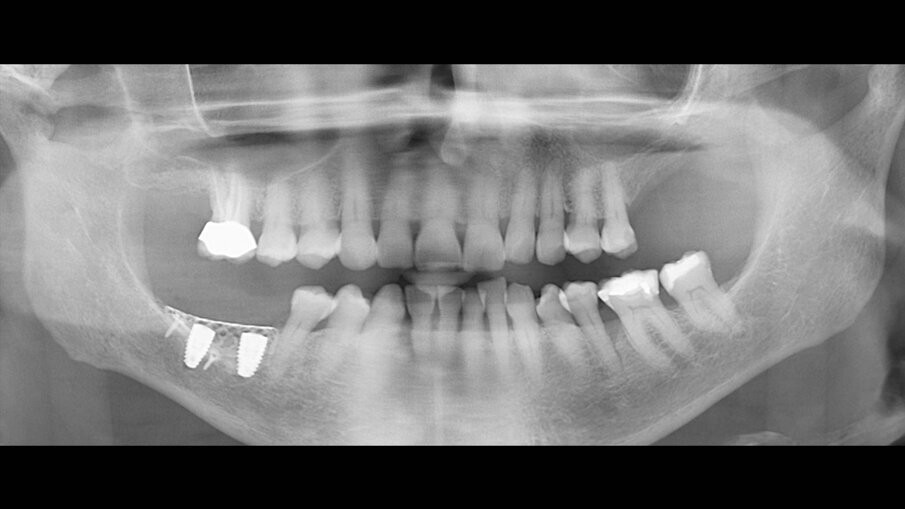

Figg. 8a, 8b_OPT e sezioni di CBCT dopo l’intervento che mostrano l’incremento osseo ottenuto.